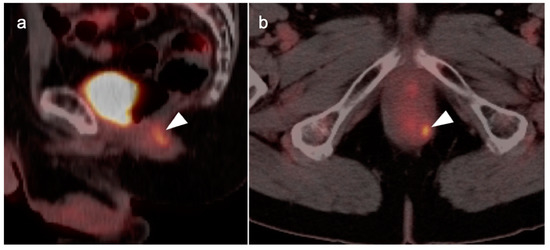

7. Adrenal Cancer